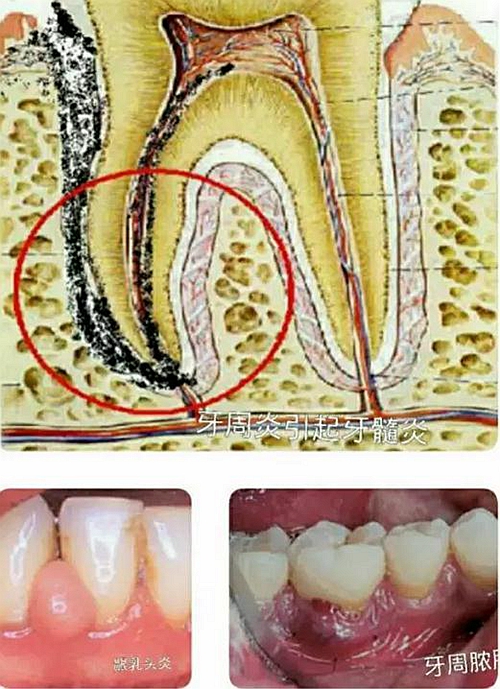

這需要與齲齒引起的牙髓炎,根尖炎時的巨痛作比較。如上組圖之上圖,齲齒是在堅硬的牙齒上面形成的,然后波及到牙神經(jīng)后引起炎癥,再向牙根方向擴散。這個過程都是在一個相對密閉的堅硬牙齒和骨頭結構里發(fā)生和進行,迅速產生的大量炎癥產物形成巨大壓力,引起牙神經(jīng)或骨神經(jīng)巨痛。

如上組圖之下圖,為牙周病發(fā)生發(fā)展的情形。病程一般從牙齦開始,牙齦是軟組織,牙齦與牙槽骨組合的是相對開放的結構。當發(fā)生炎癥時,炎癥產物形成的壓力一般較小,加之漱口,喝水以及唾液流動等,又能沖洗稀釋,所以牙周組織發(fā)炎時,多數(shù)情況下,不會引起巨痛。

牙周病雖然大多時候癥狀輕微,但也有發(fā)生劇痛的時候,如上組三圖所示,比如發(fā)生齦乳頭炎,牙周膿腫及牙周炎引起牙髓炎時。此時患者必然會去看牙醫(yī)的,因為真的很疼,但是大多數(shù)患者寧愿選擇相信這些只是局限性牙病,而不愿去想,其實這是全口牙周病在局部的急性發(fā)作反應。因此再次錯過治療控制的機會。